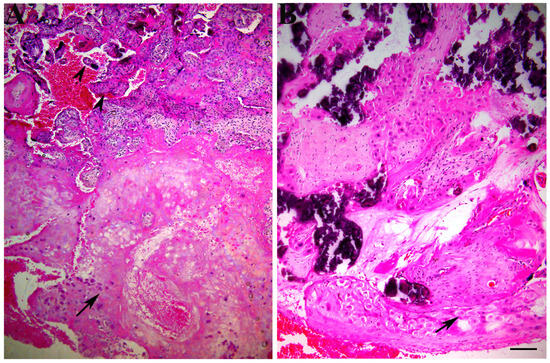

| GZMK | FasL | IFN-γ | ||

|---|---|---|---|---|

| CD8 + T cells | +++/f | −/n | −/n | |

| NK + cells | +++/f | −/n | −/n | |

| Control | Villous trophoblast | +/d | +++/d | +/f |

| Extravillous trophoblast | +/d | ++/d | +/f | |

| CD8 + Tcells | +++/f | −/n | −/n | |

| Preeclampsia | NK + cells | +++/f | −/n | −/n |

| Villous trophoblast | ++/d | ++/d | +/f | |

| Extravillous trophoblast | +++/d | +/d | +/f |